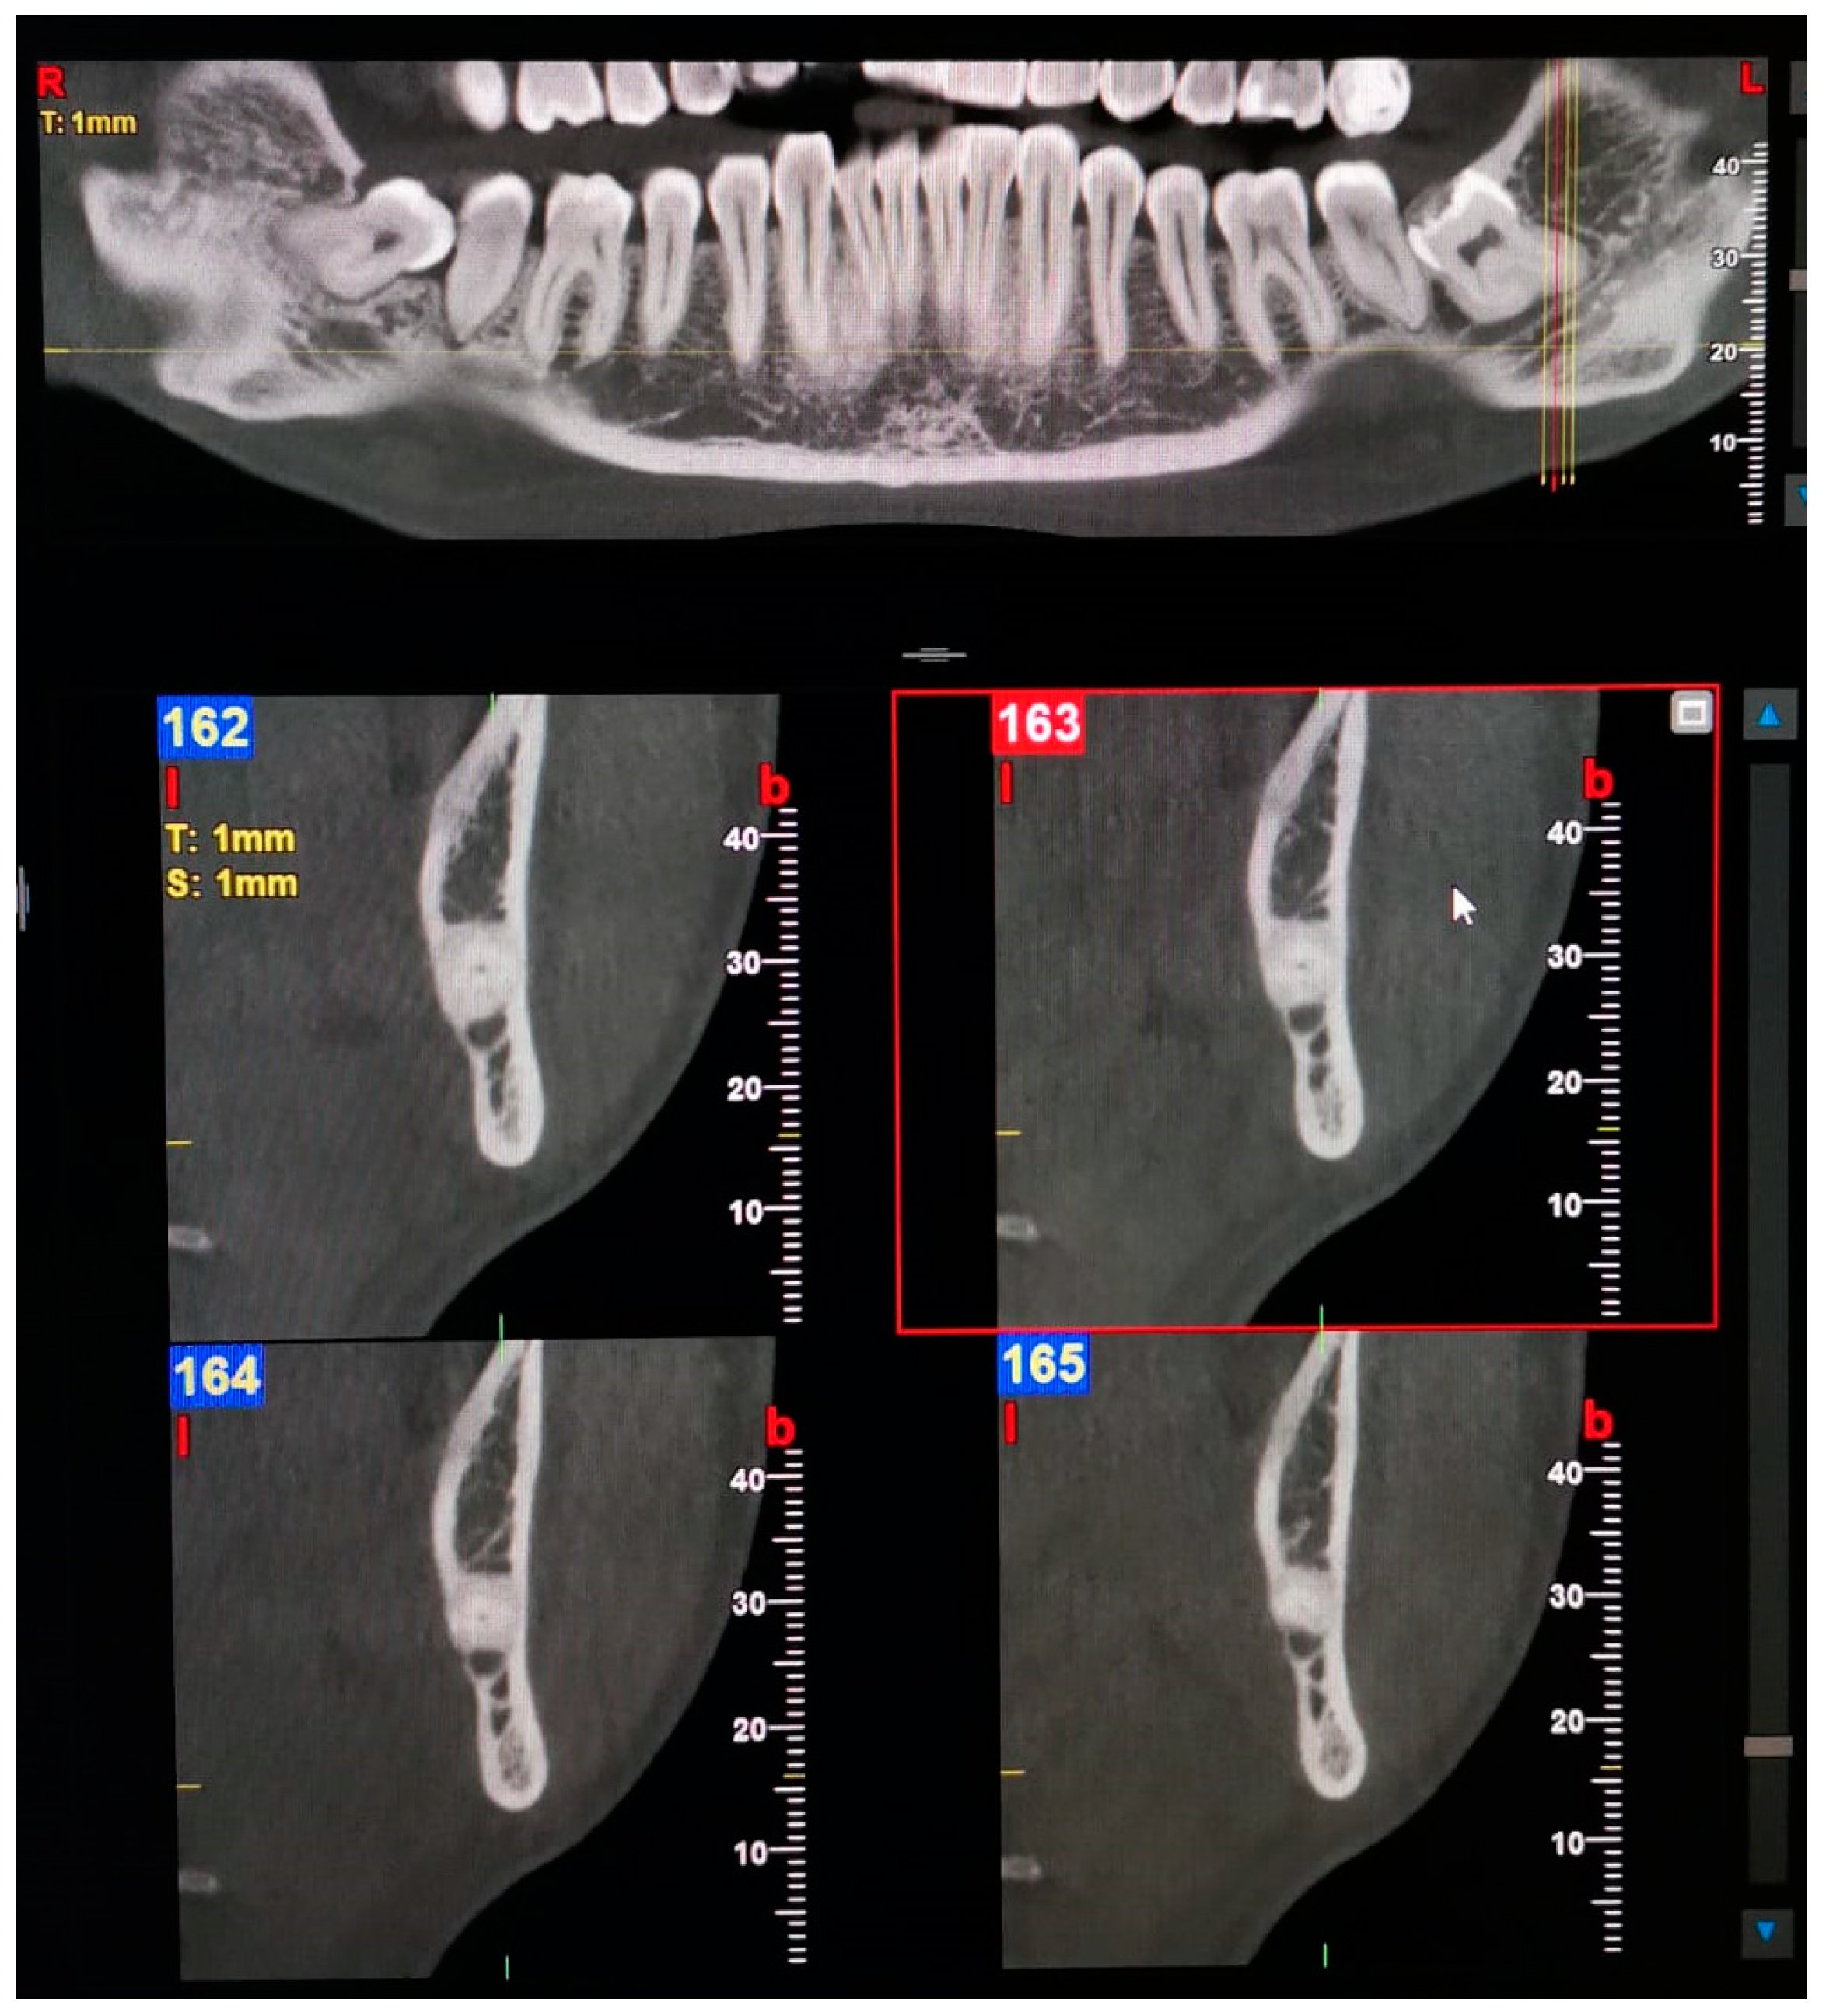

| 3—Forward | Without confluence: The forward canal, which bifurcates from the mandibular canal in the mandibular ramus region, courses forward to the second molar region.  With confluence: The forward canal, which bifurcates from the mandibular canal in the mandibular ramus, courses anteriorly and then rejoins the main mandibular canal.  |

| 4—Buccolingual | The buccal canal, which bifurcates from the mandibular canal in the mandibular ramus, courses bucco-inferiorly.  Lingual canal: The lingual canal, which bifurcates from the mandibular canal in the mandibular ramus, courses lingually and then penetrates through the lingual cortical bone.  |